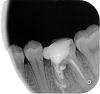

vernon Опубликовано 17 апреля, 2011 Поделиться Опубликовано 17 апреля, 2011 На этой неделе проделали гемисекцию нижней левой 6-ки, остался олин корень, врач предлагает потом штифт и коронку. Этот зуб лечили очень долго, практически полгода, я сглупила, выложила на одном из форумов панорамный снимок, мне посовтовали заняться лечением всех 6-к - запломбированы давно, более 10 лет назад, до лечения не беспокоили, но поскольку до этого один зуб потеряла, решила не рисковать и заняться лечением. В результате получилось то, что на рентгене. Уже сейчас прочитала у вас на форуме, что старые зарезорциненные каналы лучше не трогать, но мой врач решил попытаться со всеми 3 шестерками, в результате один зуб прошел все каналы и уже запломбировал, првада теперь не знаю, какой будет итог, а еще 1 верхняя 6-ка с еще 1 пройденным каналом, 2 - не пройдены, но уже решили так их оставить.У меня вопрос - может имеет смысл удалить половину оставшегося зуба и не тратить лишние деньги на вкладку и коронку? Хотя прошло уже 4 дня, болезненность зуба осталась и подчелюстные узлы до сих пор увеличены.Заранее большое спасибо. Ссылка на комментарий

Dr. Surkin Опубликовано 17 апреля, 2011 Поделиться Опубликовано 17 апреля, 2011 На этой неделе проделали гемисекцию нижней левой 6-ки, остался олин корень, врач предлагает потом штифт и коронку. Этот зуб лечили очень долго, практически полгода, я сглупила, выложила на одном из форумов панорамный снимок, мне посовтовали заняться лечением всех 6-к - запломбированы давно, более 10 лет назад, до лечения не беспокоили, но поскольку до этого один зуб потеряла, решила не рисковать и заняться лечением. В результате получилось то, что на рентгене. Уже сейчас прочитала у вас на форуме, что старые зарезорциненные каналы лучше не трогать, но мой врач решил попытаться со всеми 3 шестерками, в результате один зуб прошел все каналы и уже запломбировал, првада теперь не знаю, какой будет итог, а еще 1 верхняя 6-ка с еще 1 пройденным каналом, 2 - не пройдены, но уже решили так их оставить.У меня вопрос - может имеет смысл удалить половину оставшегося зуба и не тратить лишние деньги на вкладку и коронку? Хотя прошло уже 4 дня, болезненность зуба осталась и подчелюстные узлы до сих пор увеличены.Заранее большое спасибо. Гемисекция 6-ки , когда есть и 5 и 7 и они никак не будут объеденены одной конструкцией - бессмысленное мучение и вред. Это раньше до эры имплантатов делали, когда других вариантов сохранить опору в жевательном отделе не было. И одиночные коронки на них предпочитали не ставить. Так что я за удаление остатка.... Ссылка на комментарий